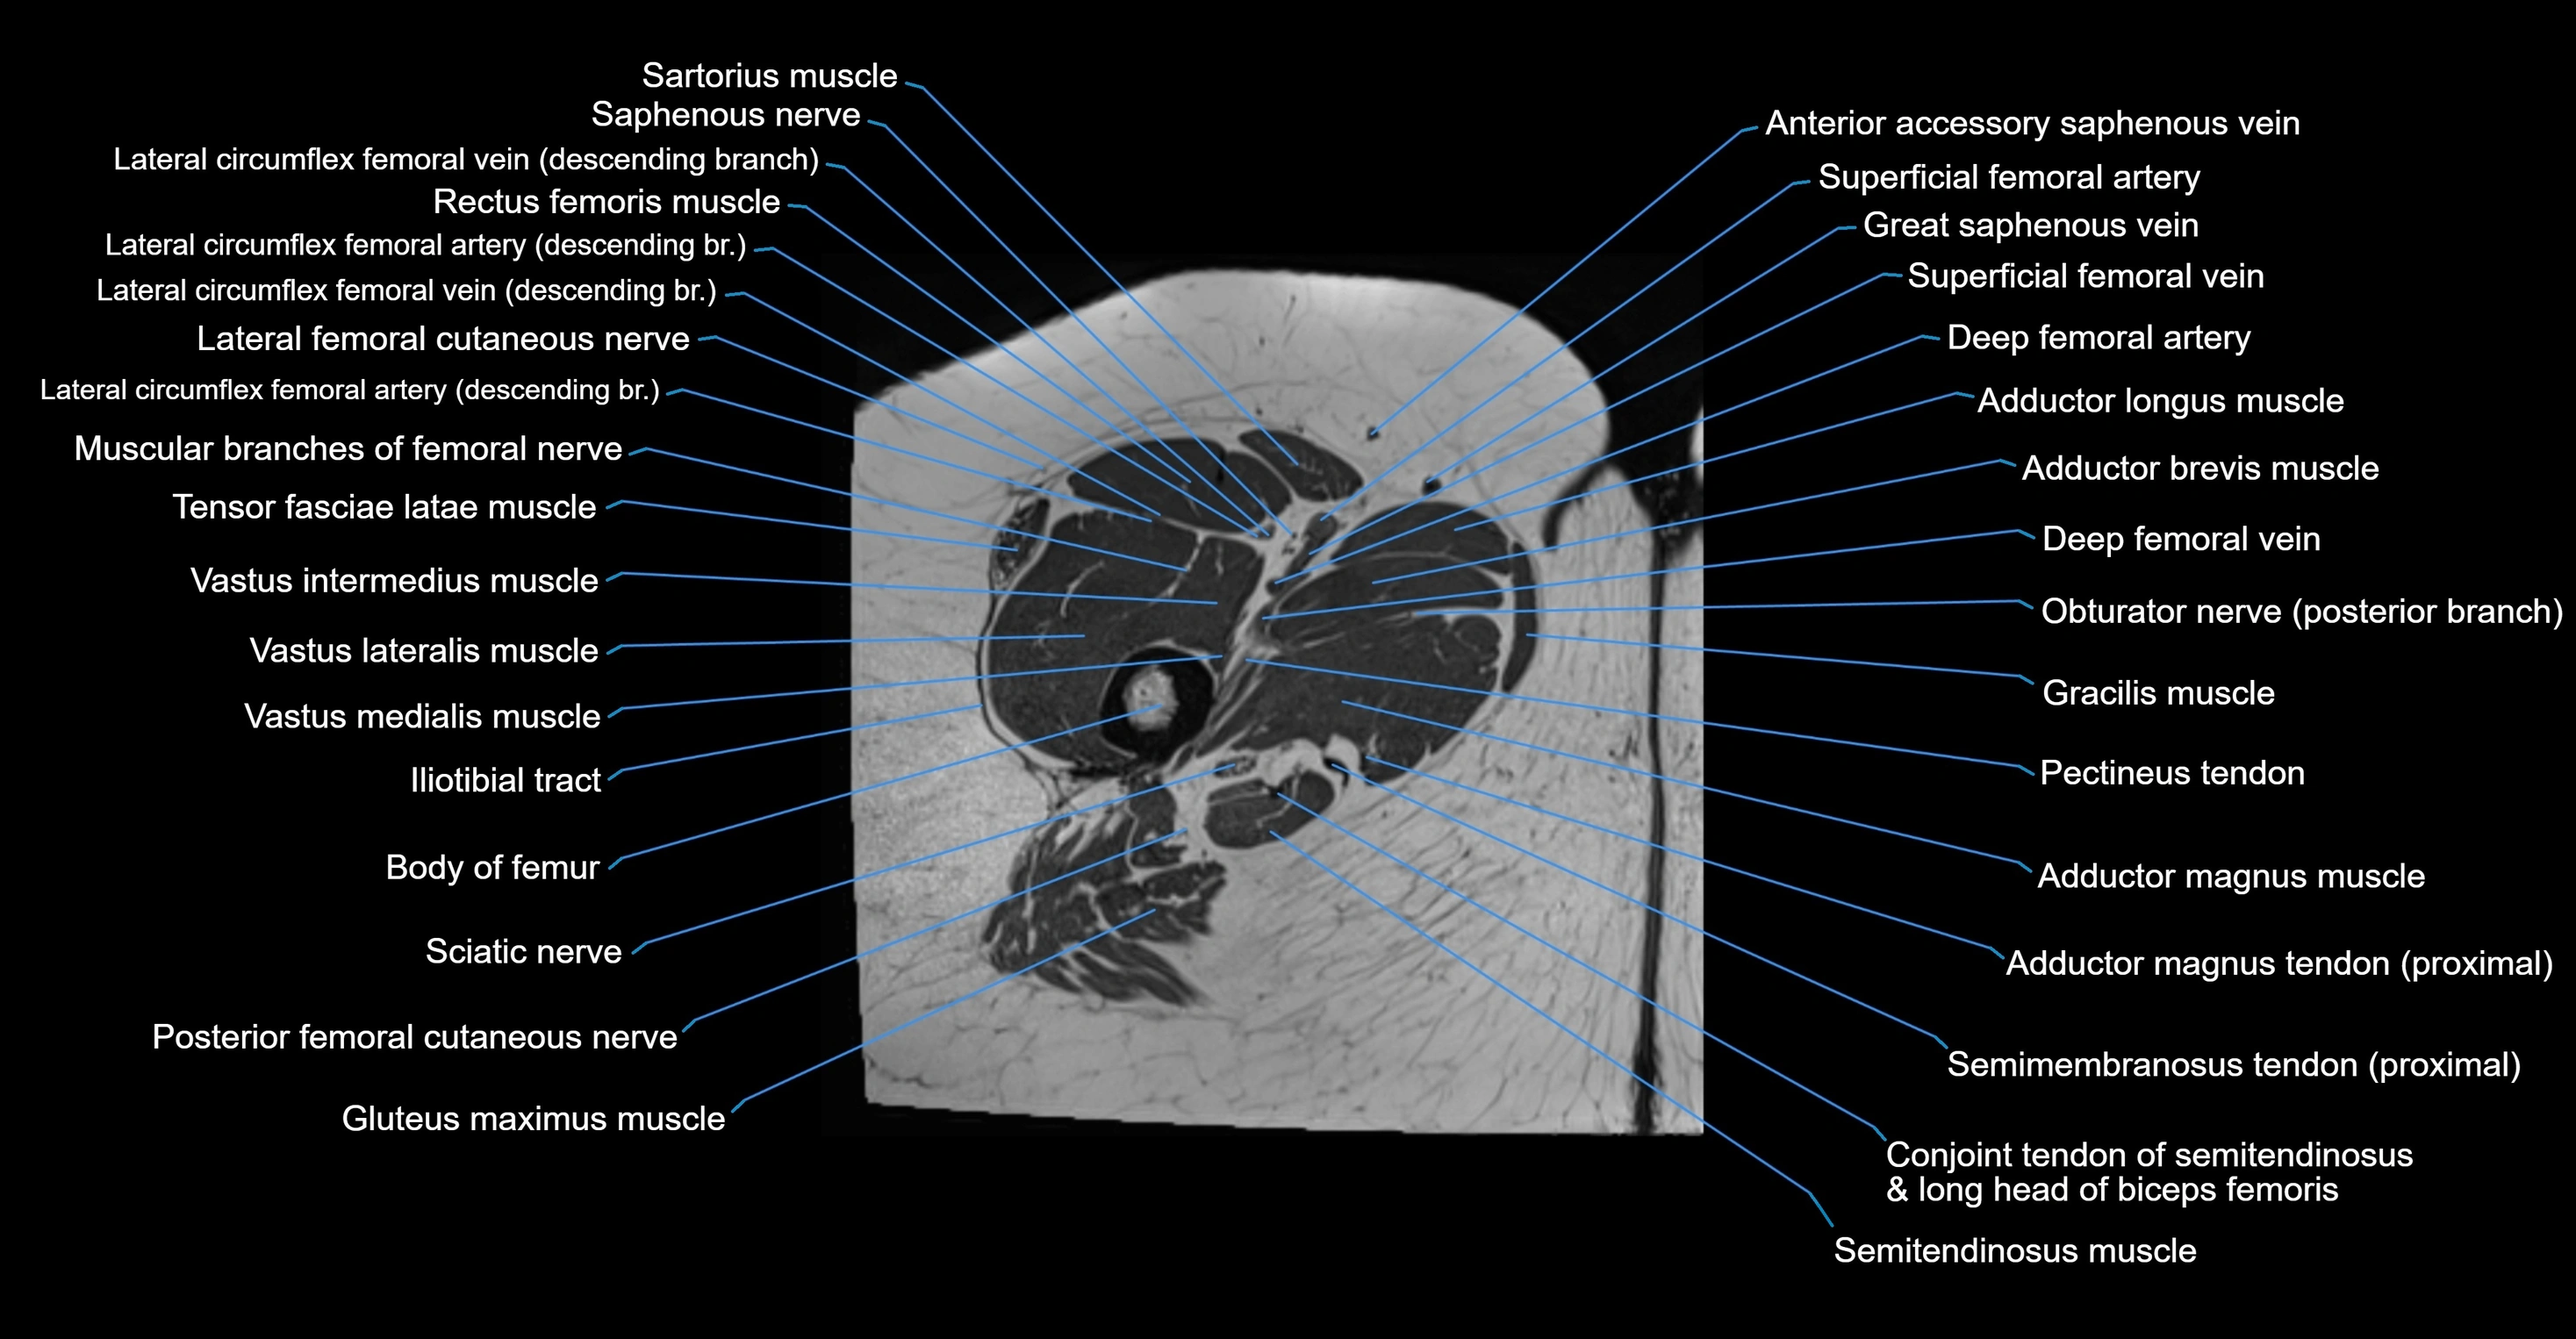

- Body of femur

- Iliotibial tract

- Muscular branches of femoral nerve

- Posterior femoral cutaneous nerve

- Saphenous nerve

- Sartorius muscle

- Semimembranosus tendon (proximal)

- Tensor fasciae latae muscle

- Vastus intermedius muscle

- Vastus lateralis muscle

- Vastus medialis muscle